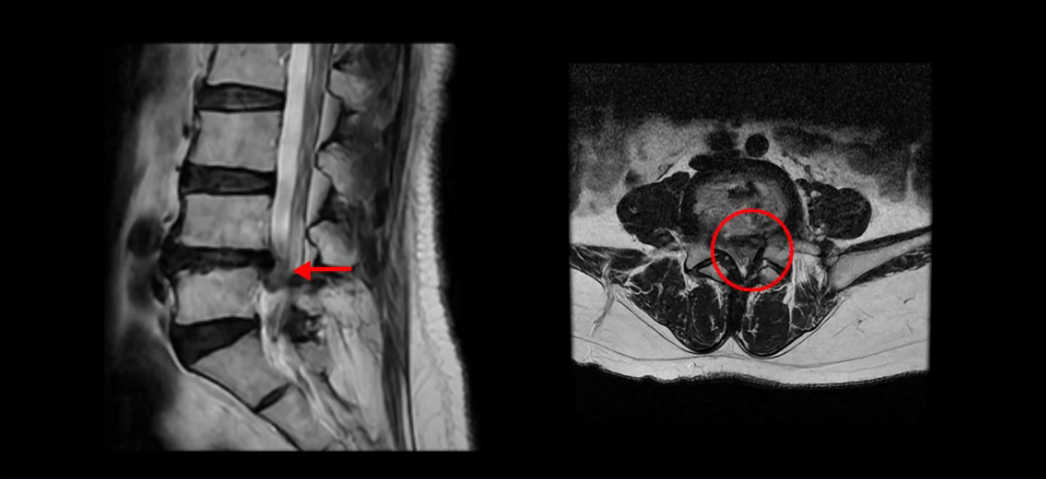

이분 MRI를 보시면 아주 심하게 디스크가 터져서 밀려나오면서 밑으로 흘러내렸습니다. 단면을 보시면 신경 공간의 거의 대부분을 차지하고 있을 정도로 파열이 심합니다.

그럼에도 불구하고 통증만 극심하지 마비증상은 없는 상태셨습니다. 다시 설명 드리지만 저희 모커리 치료는 디스크 파열로 인해 마비가 있든 없든 크게 치료 결과에 차이가 없습니다. 그러니까 마비증상이 있다고, 또는 마비증상이 생길까 봐 걱정돼서 수술을 서두르시거나 고민하실 필요가 없습니다.